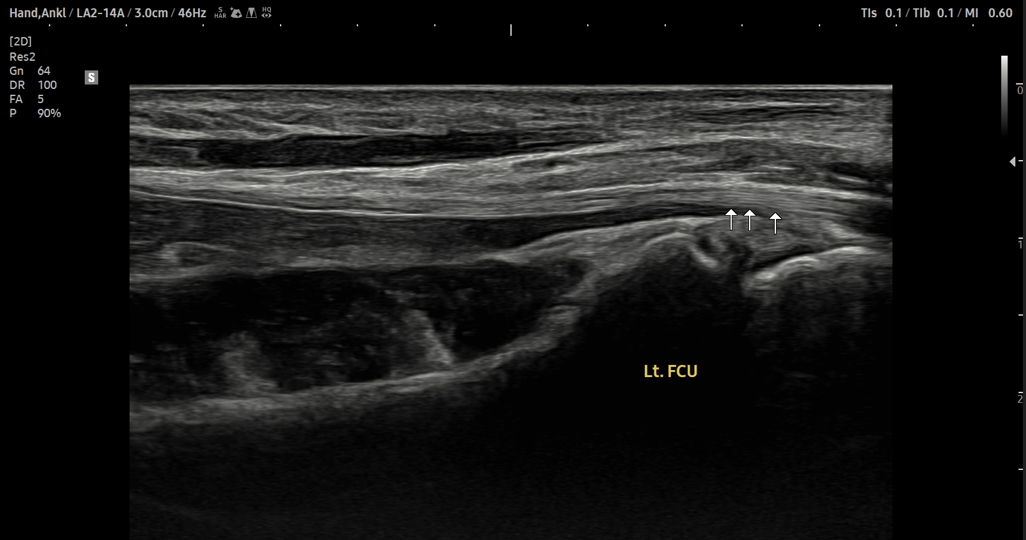

- 치료기간 : 25 . 9 . 27 ~ 25 . 11 . 19

- 치료횟수 : 12 회